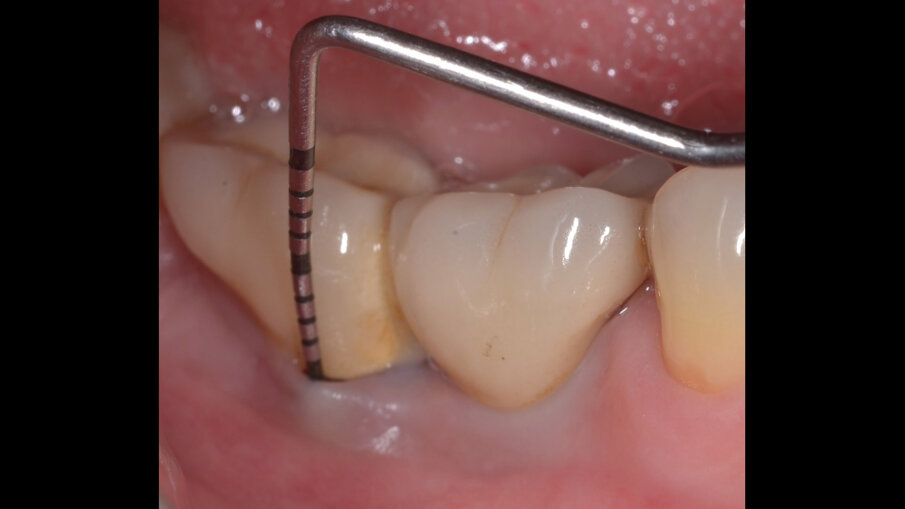

Il paziente, di sesso maschile e di 48 anni di età, è in buone condizioni di salute generale ma, a distanza di 10 anni dall’inserimento, presenta due impianti endossei, in posizione 4.6 e 4.7 con uniforme perdita ossea e con sondaggi di profondità variabile tra 6 e 9 mm accompagnati da sanguinamento, con tessuti marginali che mostrano importanti aspetti infiammatori, causa di sintomatologia dolorosa per il paziente (Figg. 1a-f).

I siti interessati sono stati strumentati per via non chirurgica, utilizzando strumenti manuali, strumenti ultrasonici e air polishing con eritritolo. Al termine della seduta è stato applicato il gel di ozono (Ozosan Gel - Bioactiva) all’interno delle tasche, lasciando agire il dispositivo per 8 minuti, quindi eseguendo lavaggio con soluzione fisiologica. Il post-operatorio ha avuto un decorso privo di dolore con rapida remissione della sintomatologia soggettiva. Il paziente è stato inserito in un programma di mantenimento parodontale trimestrale. A distanza di 6 mesi dal trattamento non chirurgico della perimplantite, i siti si presentano stabili con profondità di sondaggio ridotta tra i 3 e i 5 mm con assenza completa di sanguinamento al sondaggio (Figg. 1g-m).